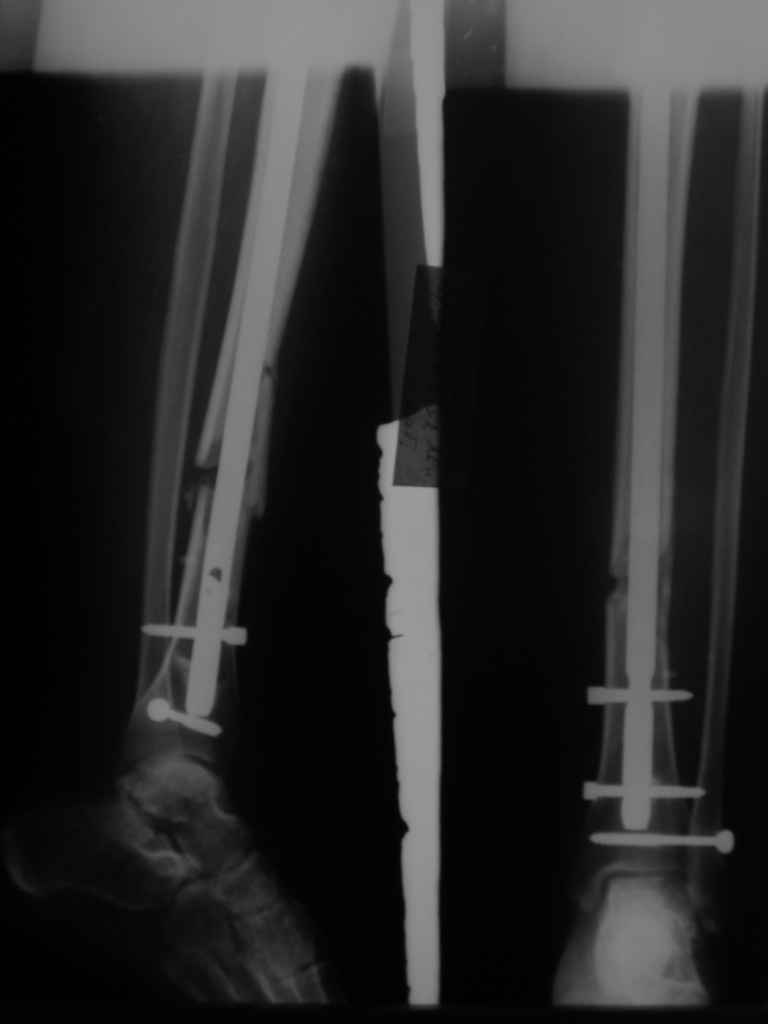

Посмотрев на клинический случай с винтообразным переломом ББ и МБ костей, возник вопрос о целесообразности динамизации фиксатора при подобном типе перлома.

Винтообразный перелом создает обширную зону межфрагментарного контакта, что является благоприятным условием для консолидации, если в ожидаемые 8-10 недель мозолеообразования не наблюдается, то динамизация приводит к *соскальзыванию* проксимального фрагмента- вторичному смещению, величина которого и определяется размером овального окна гвоздя.

Логичным, на мой взгляд, в подобной ситуации является не динамизация гвоздя, а смена гвоздя на больший размер с рассверливанием.

Динамизация скорее показана при поперечных/ short oblique типах, когда зона межфрагментарного контакта ограничена, нет риска вторичного смещения отломков.